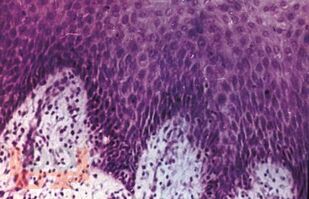

В очередной книге серии "Карманный справочник врача" известным автором, профессором И. К. Луцкой компактно освещена проблема поражений слизистой оболочки полости рта.

В первой части книги рассмотрены методы обследования больного, тактика врача-стоматолога, вопросы индивидуальной гигиены полости рта. Вторая часть содержит характеристики основных элементов поражения СОПР, проявления на СОПР различных заболеваний. Приведены общие схемы обследования, принципы диагностики и рекомендации по выбору лечебных мероприятий на основе течения и клинических особенностей заболевания.